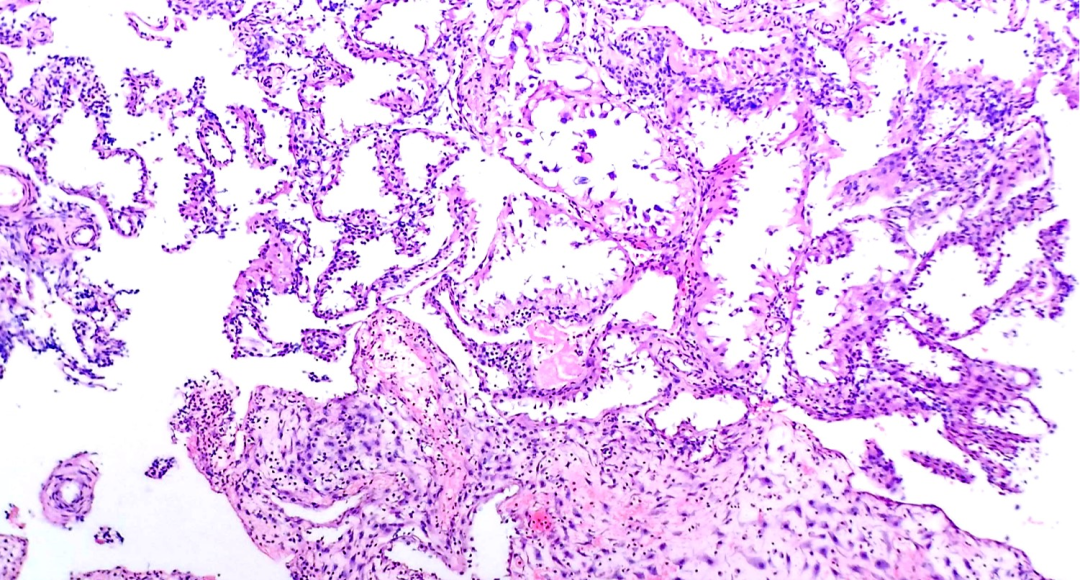

分泌晚期 排卵后9-14天

分泌中-晚期

低倍镜下螺旋动脉显著,这不仅是由于螺旋动脉管壁增厚,更主要的是由于其周围有前蜕膜间质细胞套。前蜕膜细胞最初位于螺旋动脉的周围,然后扩大并在浅表子宫内膜间质中形成前蜕膜细胞岛,晚期分泌期开始的标志。在晚期分期的终末,这些蜕膜岛逐渐融合,月经即将来临时被间质出血所分隔。伴随着子宫内膜间质进行性的前蜕膜化,间质颗粒细胞数目增加。